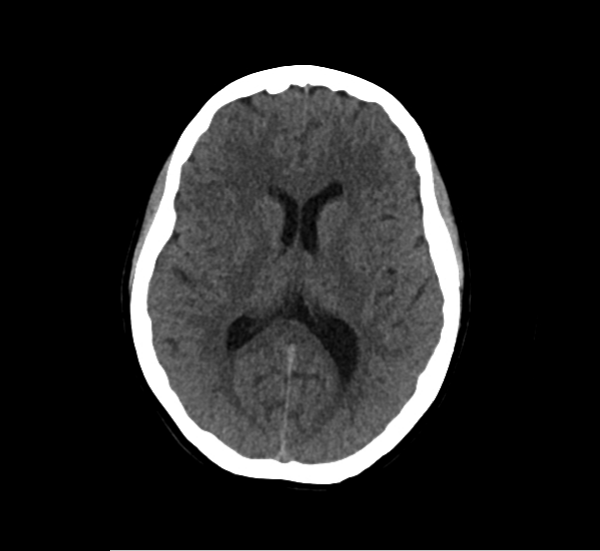

CT Brain Anatomy